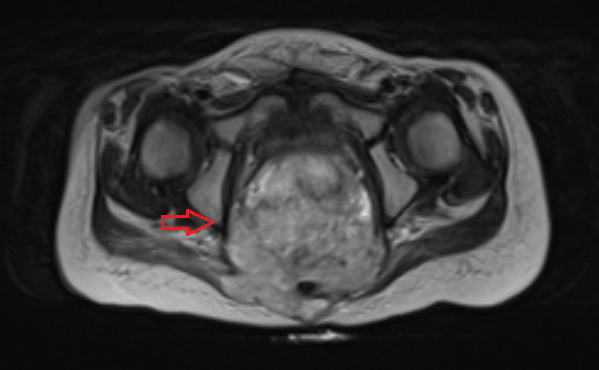

После получения гистологического заключения о характере опухоли, данных обследования: КТ грудной клетки, брюшной полости, КТ/МРТ малого таза, уровень опухолевых маркеров, проводится стадирование, определение прогноза, и командой специалистов принимается решение о лечебной тактике.

![Тератома яичника (МРТ)]()

Рисунок 3. – тератома яичника а –УЗИ, б — МРТ.